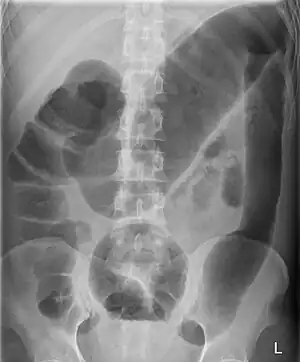

Megacolon is an abnormal dilation of the colon (also called the large intestine).[1][2] This leads to hypertrophy of the colon.[2] The dilation is often accompanied by a paralysis of the peristaltic movements of the bowel. In more extreme cases, the feces consolidate into hard masses inside the colon, called fecalomas (literally, fecal tumor), which can require surgery to be removed.

A human colon is considered abnormally enlarged if it has a diameter greater than 12 cm[3] in the cecum (it is usually less than 9 cm[4]), greater than 6.5 cm[3] in the rectosigmoid region and greater than 8 cm[3] for the ascending colon. The transverse colon is usually less than 6 cm in diameter.[4]